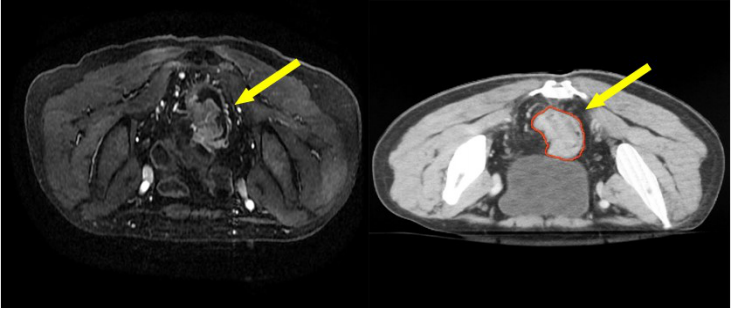

• 直腸癌的三維放療及調(diào)強(qiáng)放療靶區(qū)勾畫

直腸癌的三維放療及調(diào)強(qiáng)放療靶區(qū)勾畫

直腸癌是中國(guó)常見和高發(fā)疾病,好發(fā)于 40 歲以上人群。大部分直腸癌是散發(fā)病例,也可能源于某些遺傳病,但僅約占 5%的病因。在西方國(guó)家是常見腫瘤,在中國(guó)發(fā)病率也逐年升高,其發(fā)病率和死亡率均排在前十位。散發(fā)性直腸癌的具體病因不明,主要與遺傳因素、環(huán)境因素和生活方式有密切關(guān)系。

直腸癌的癥狀在早期通常不明顯且無(wú)特異性,隨著腫瘤進(jìn)展常見的局部癥狀包括:大便習(xí)慣改變,